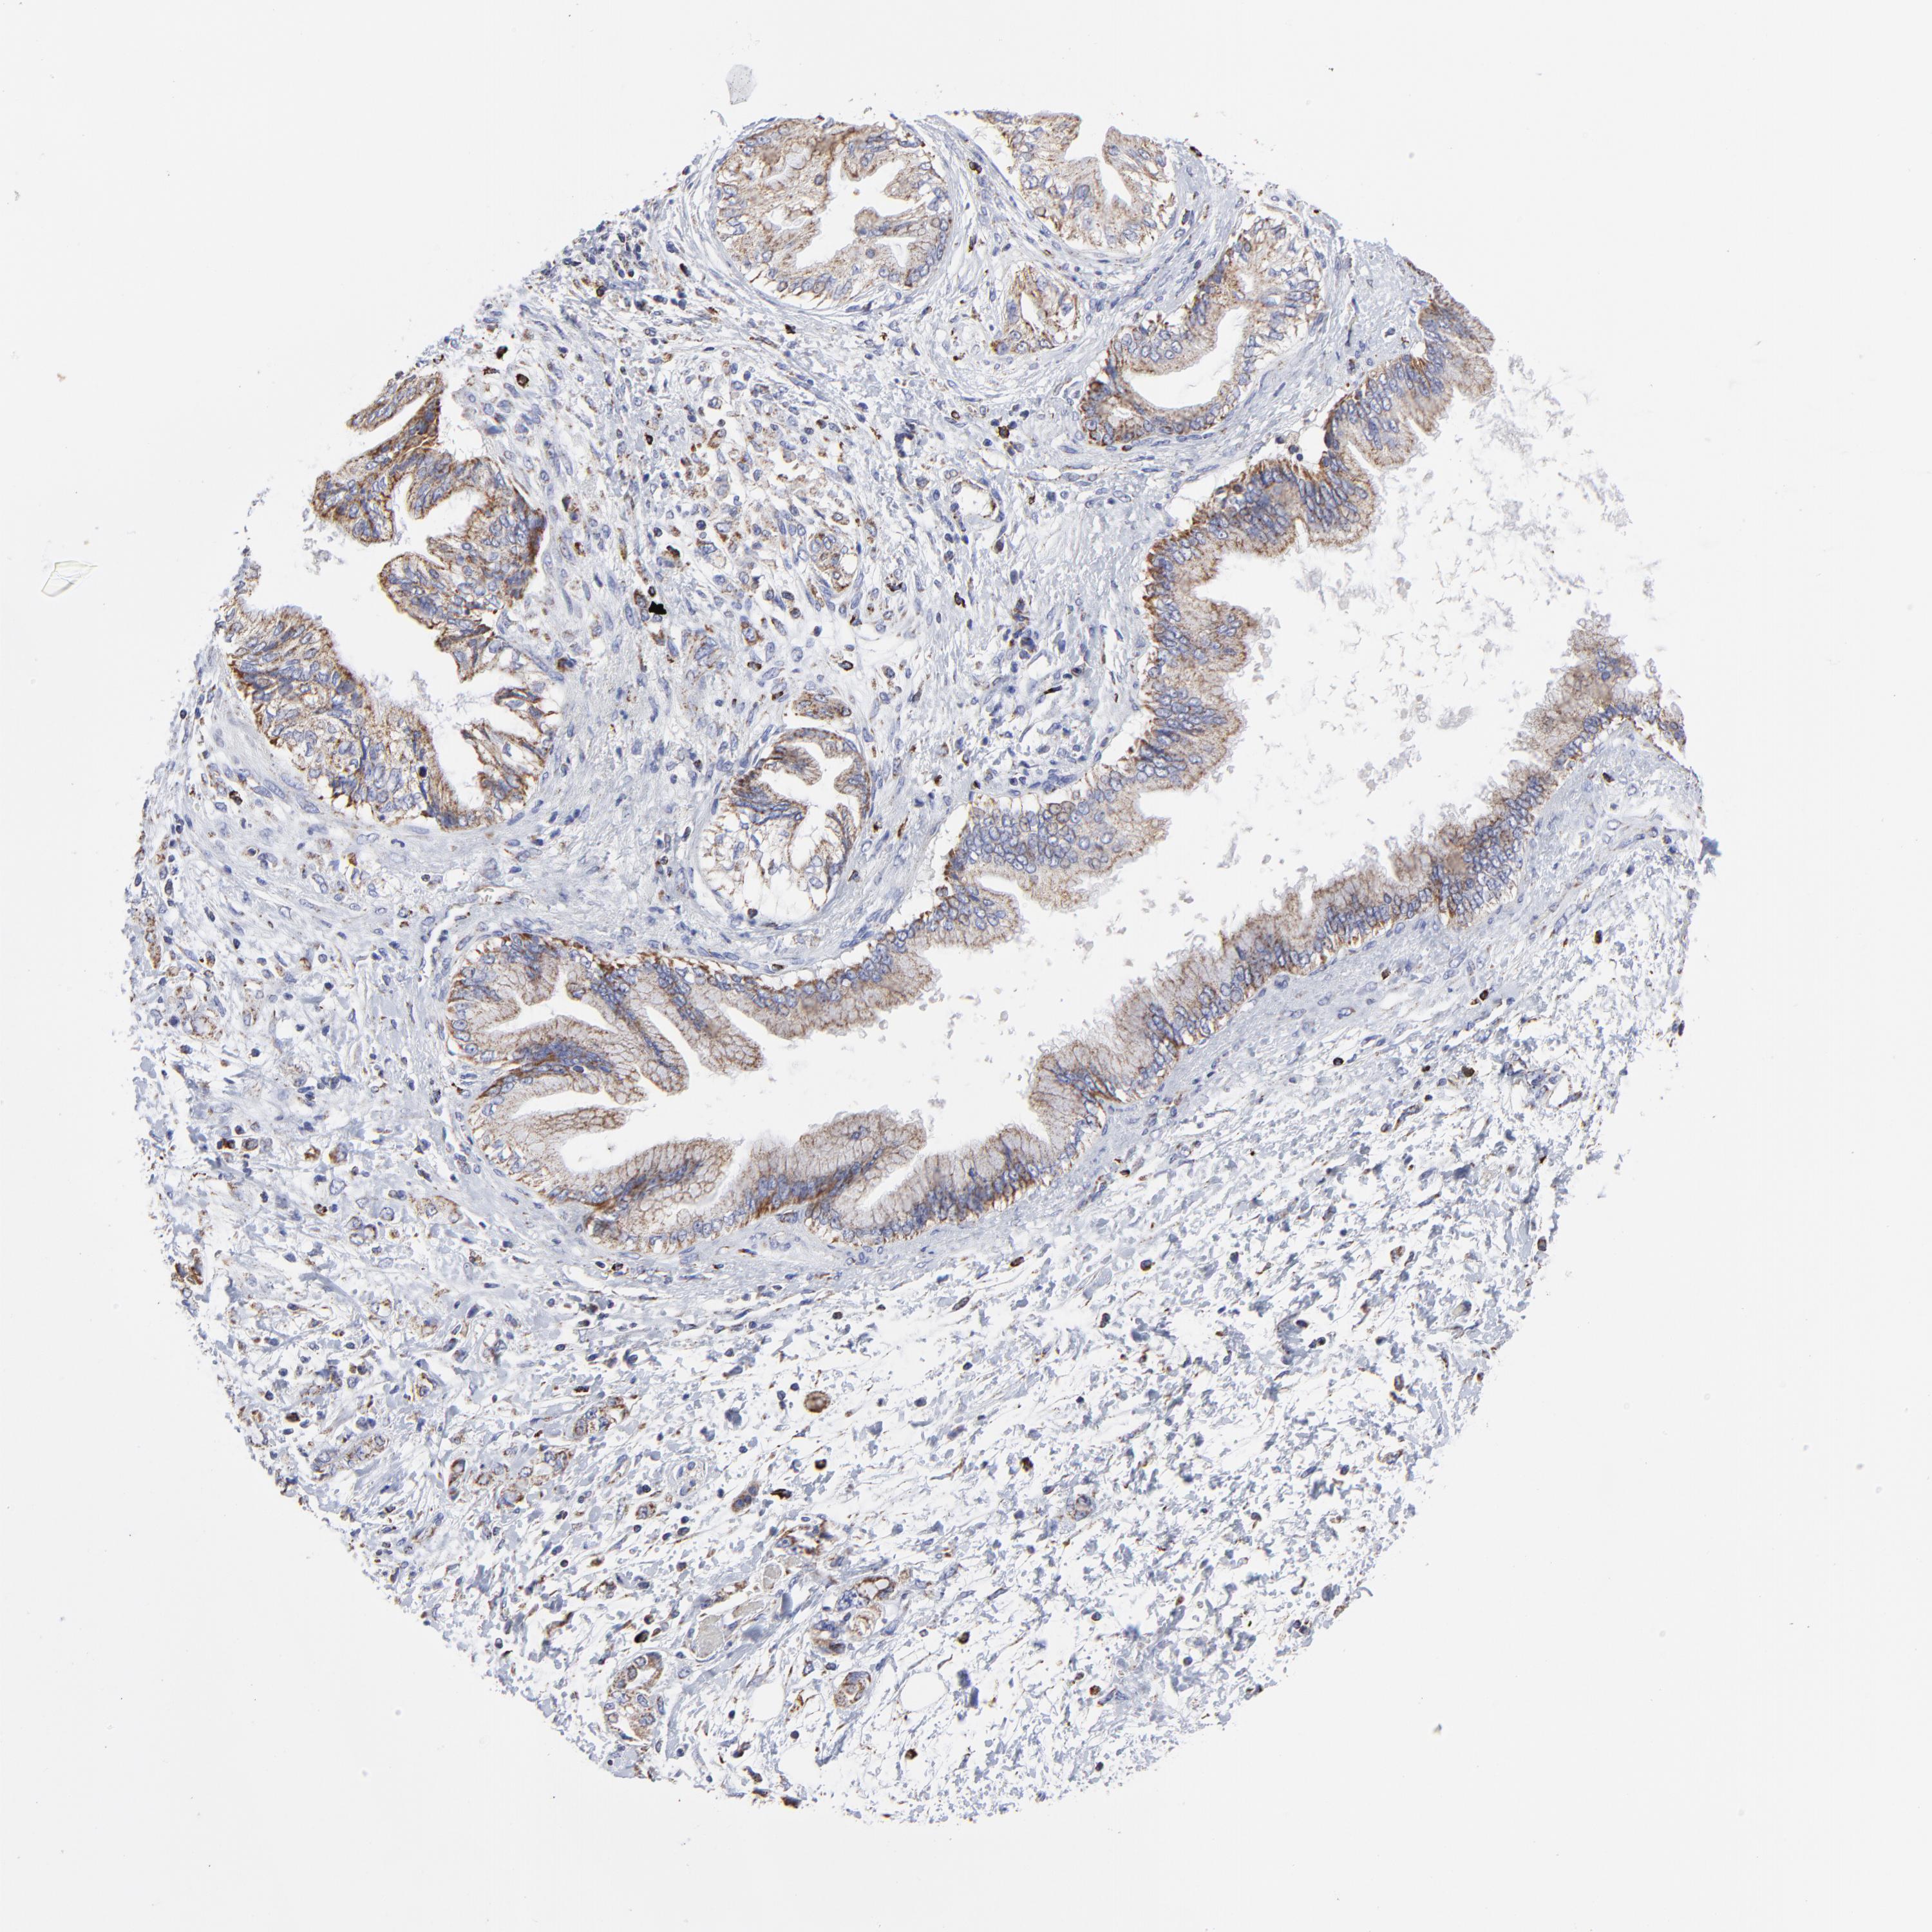

PANCREATIC CANCER - Protein expressioni

A mouse-over function shows sample information and annotation data. Click on an image to view it in a full screen mode. Samples can be filtered based on level of antibody staining by selecting one or several of the following categories: high, medium, low and not detected. The assay and annotation is described here.

Note that samples used for immunohistochemistry by the Human Protein Atlas do not correspond to samples in the TCGA dataset.

Antibody stainingi

Antibody staining in the annotated cell types in the current human tissue is reported as not detected, low, medium, or high, based on conventional immunohistochemistry profiling in selected tissues. This score is based on the combination of the staining intensity and fraction of stained cells.

Each image is clickable and will lead to virtual microscopy that enables deeper exploration of all samples and also displays staining intensity scores, fraction scores and subcellular localization as well as patient and tissue information for each sample.

Antibody HPA001931

Antibody CAB026191

Staining

High

Medium

Low

Not detected

Intensity

Strong

Moderate

Weak

Negative

Quantity

>75%

75%-25%

<25%

None

Location

Nuclear

Cytoplasmic/membranous

Cytoplasmic/membranous,nuclear

Adenocarcinoma, NOS